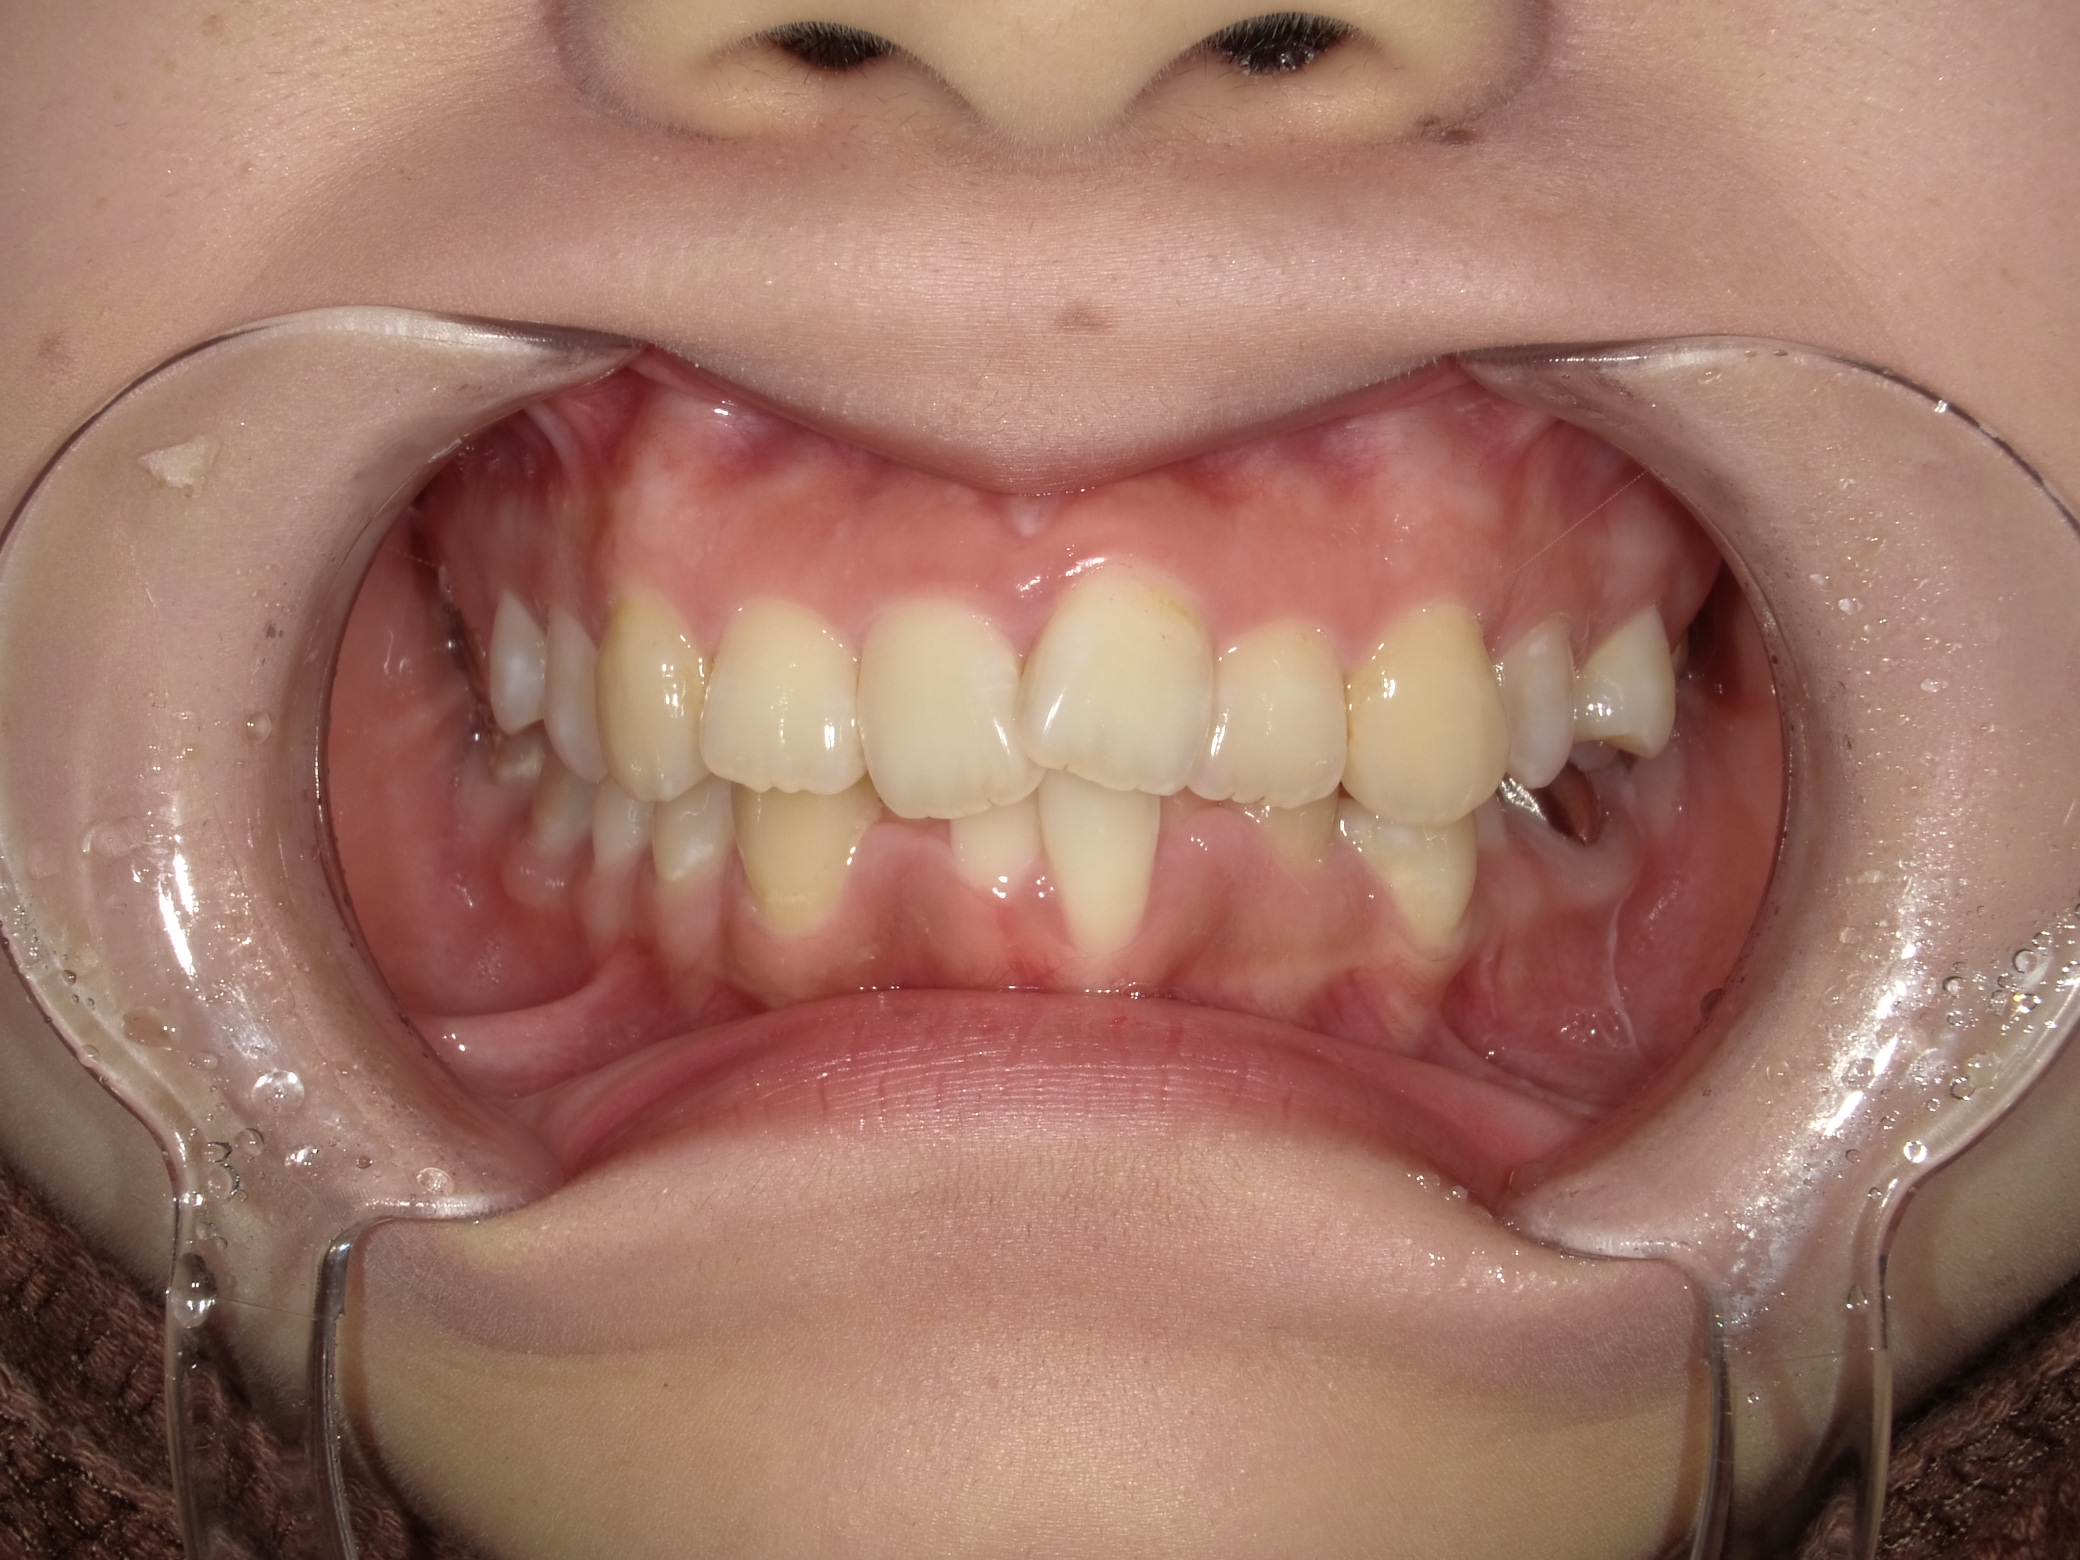

症例①|前歯の突出感(出っ歯)と歯の重なりをインビザラインで改善した症例

前歯の突出感(出っ歯)と、下の歯の重なり(叢生)を併発していた状態を、インビザラインで治療したケースです。

■ 治療前の状態(Before)

治療前は上顎前歯の突出感が目立ち、前歯が前方に傾いている状態でした。

あわせて下顎の歯並びには重なり(叢生)も見られ、歯列全体のバランスが乱れていました。